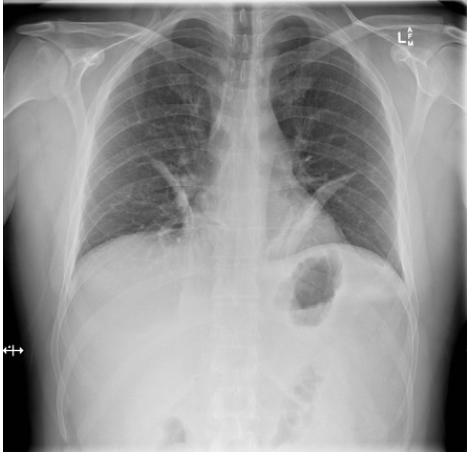

what should an xray of the lungs look like

xray of lungs with COPD

widened intercostal spaces

flattened hemidiaphragms

squared off costophrenic angles and rib angles that approach 90 degree angles

xray of lungs with atelectasis

diaphragm elevation on the collapsed side

deviation of the mediiastinum, trachea (deviated towards collapsed side

increased density of the lobe